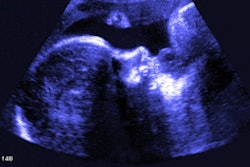

Midgut malrotation (above) and volvulus (below) can be found in pediatric patients with abdominal abnormalities. Ultrasound shows high sensitivity and specificity in diagnosing these conditions, according to research led by Dr. Haithuy Nguyen from Texas Children's Hospital. Images courtesy of Dr. Haithuy NguyenUltrasound has been touted by researchers as being noninvasive and emitting no radiation, making it suitable for young children.